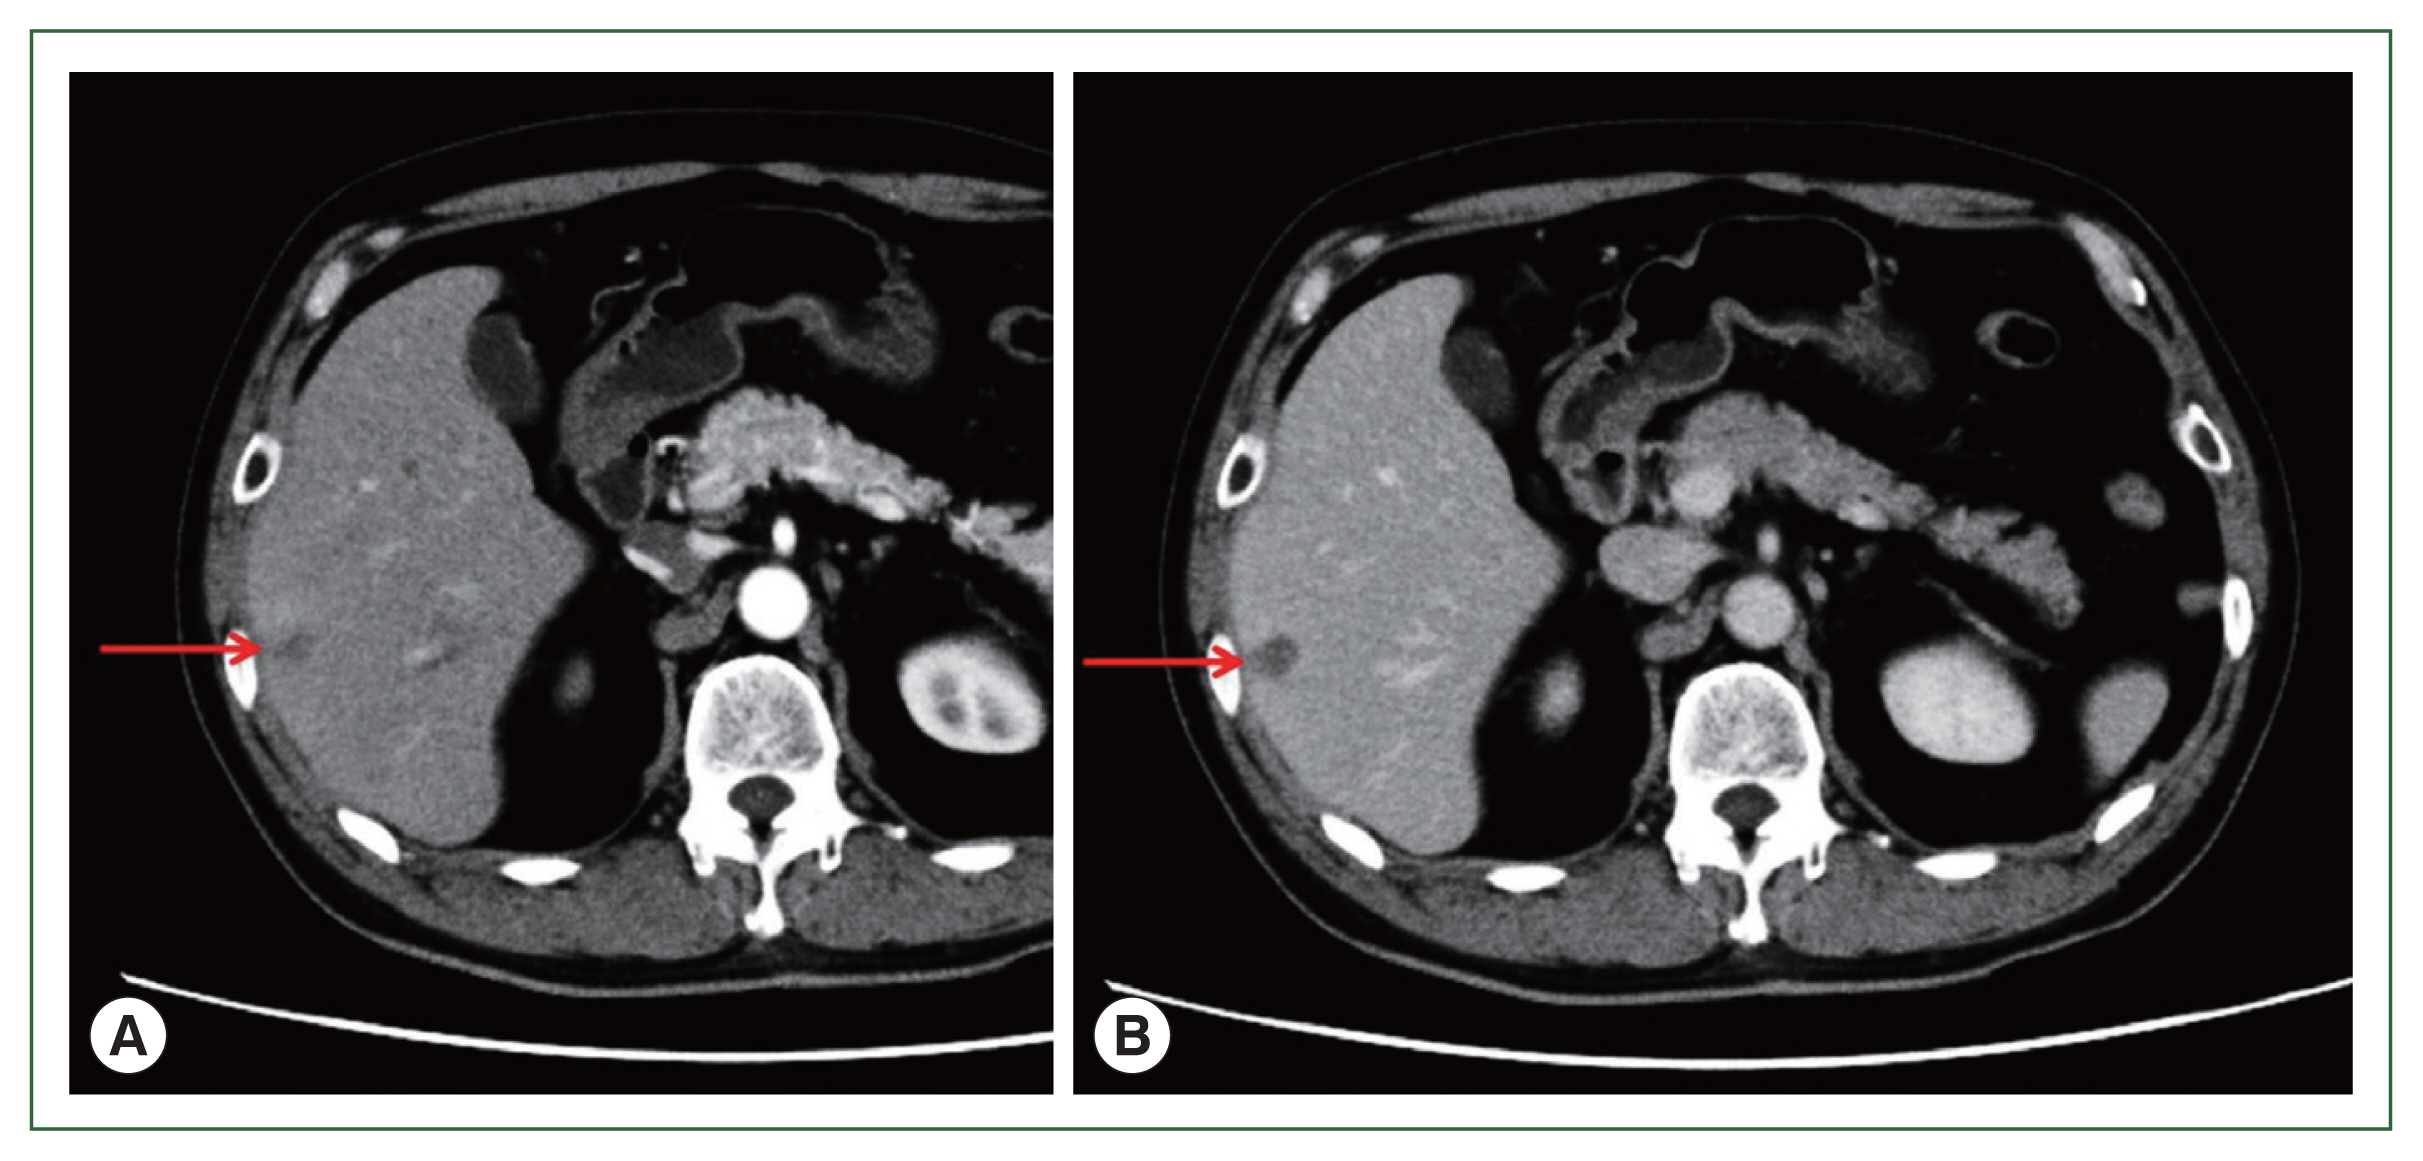

A Case of Alveolar Echinococcosis Occurring in the Hilar Bile Duct

Jinyu Yang, Zhanxue Zhao, Shuai Li, Hekai Chen

Korean J Parasitol 2019;57(5):517-520.

Published online October 31, 2019

DOI: https://doi.org/10.3347/kjp.2019.57.5.517

Echinococcosis is a disease caused by the Echinococcus species that parasitizes in humans. Alveolar echinococcosis (AE) which is caused by Echinococcus multilocularis is harmful to humans. AE mainly occurs in the liver and can be transferred to retroperitoneal lymph nodes, lung, brain, bone, spleen and other organs through lymphatic and blood vessels. Cholangiocarcinoma can occur in the intrahepatic and extrahepatic bile ducts and is more common in the hilar. We reported a case of hilar bile duct alveolar echinococcosis which was originally misdiagnosed an cholangiocarcinoma.